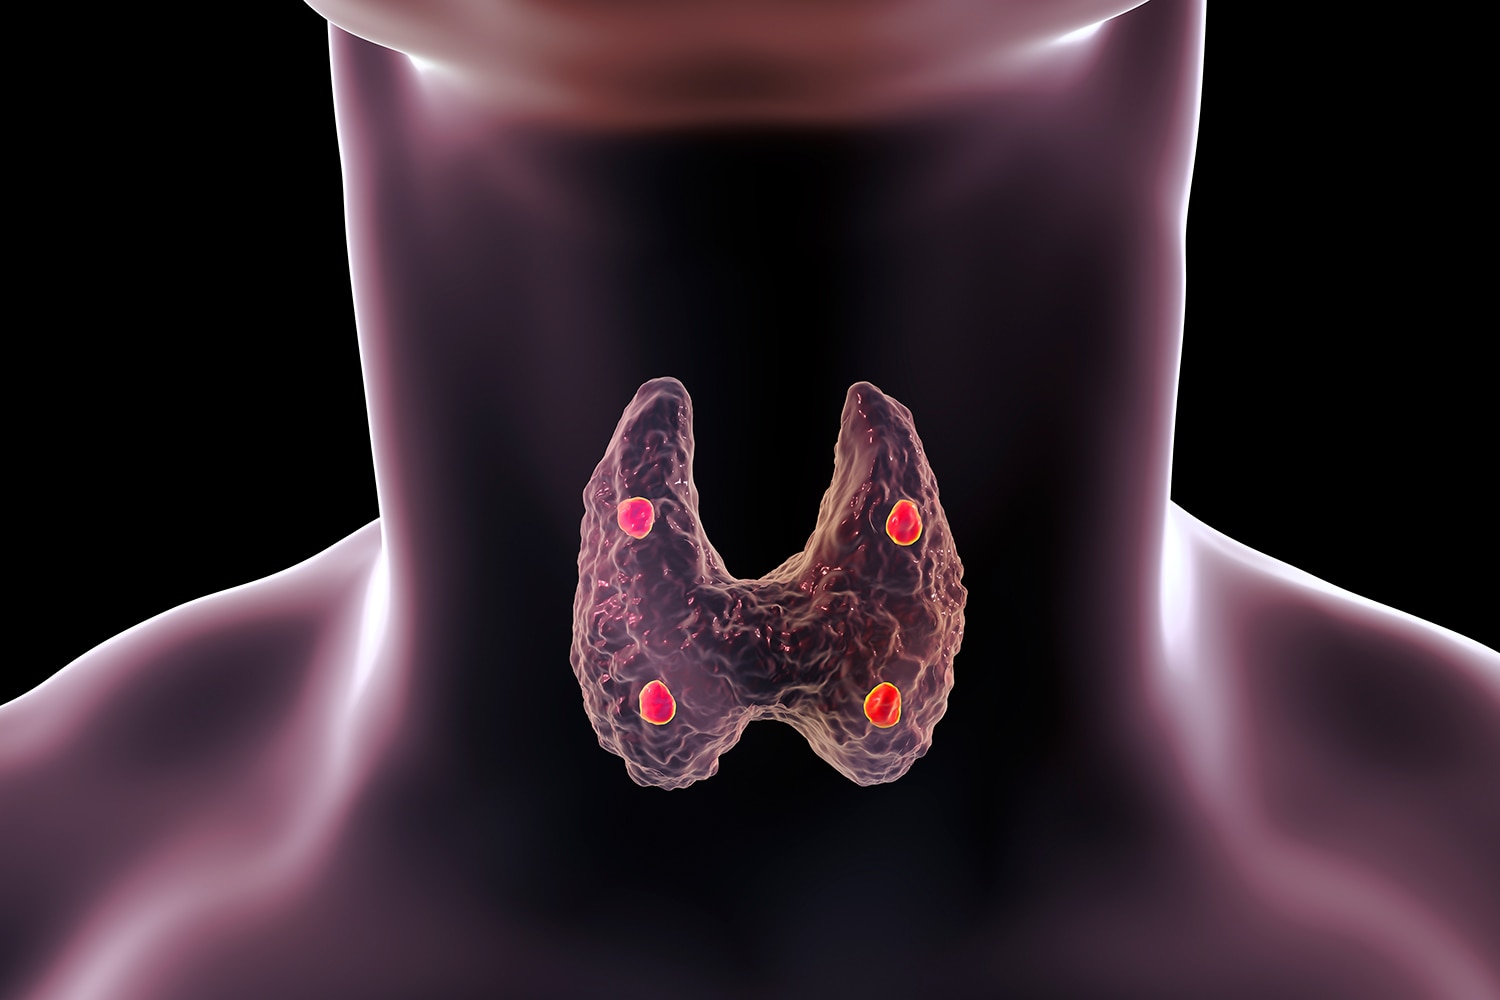

Иллюстрации и схемы по остеопорозу и паращитовидной железе